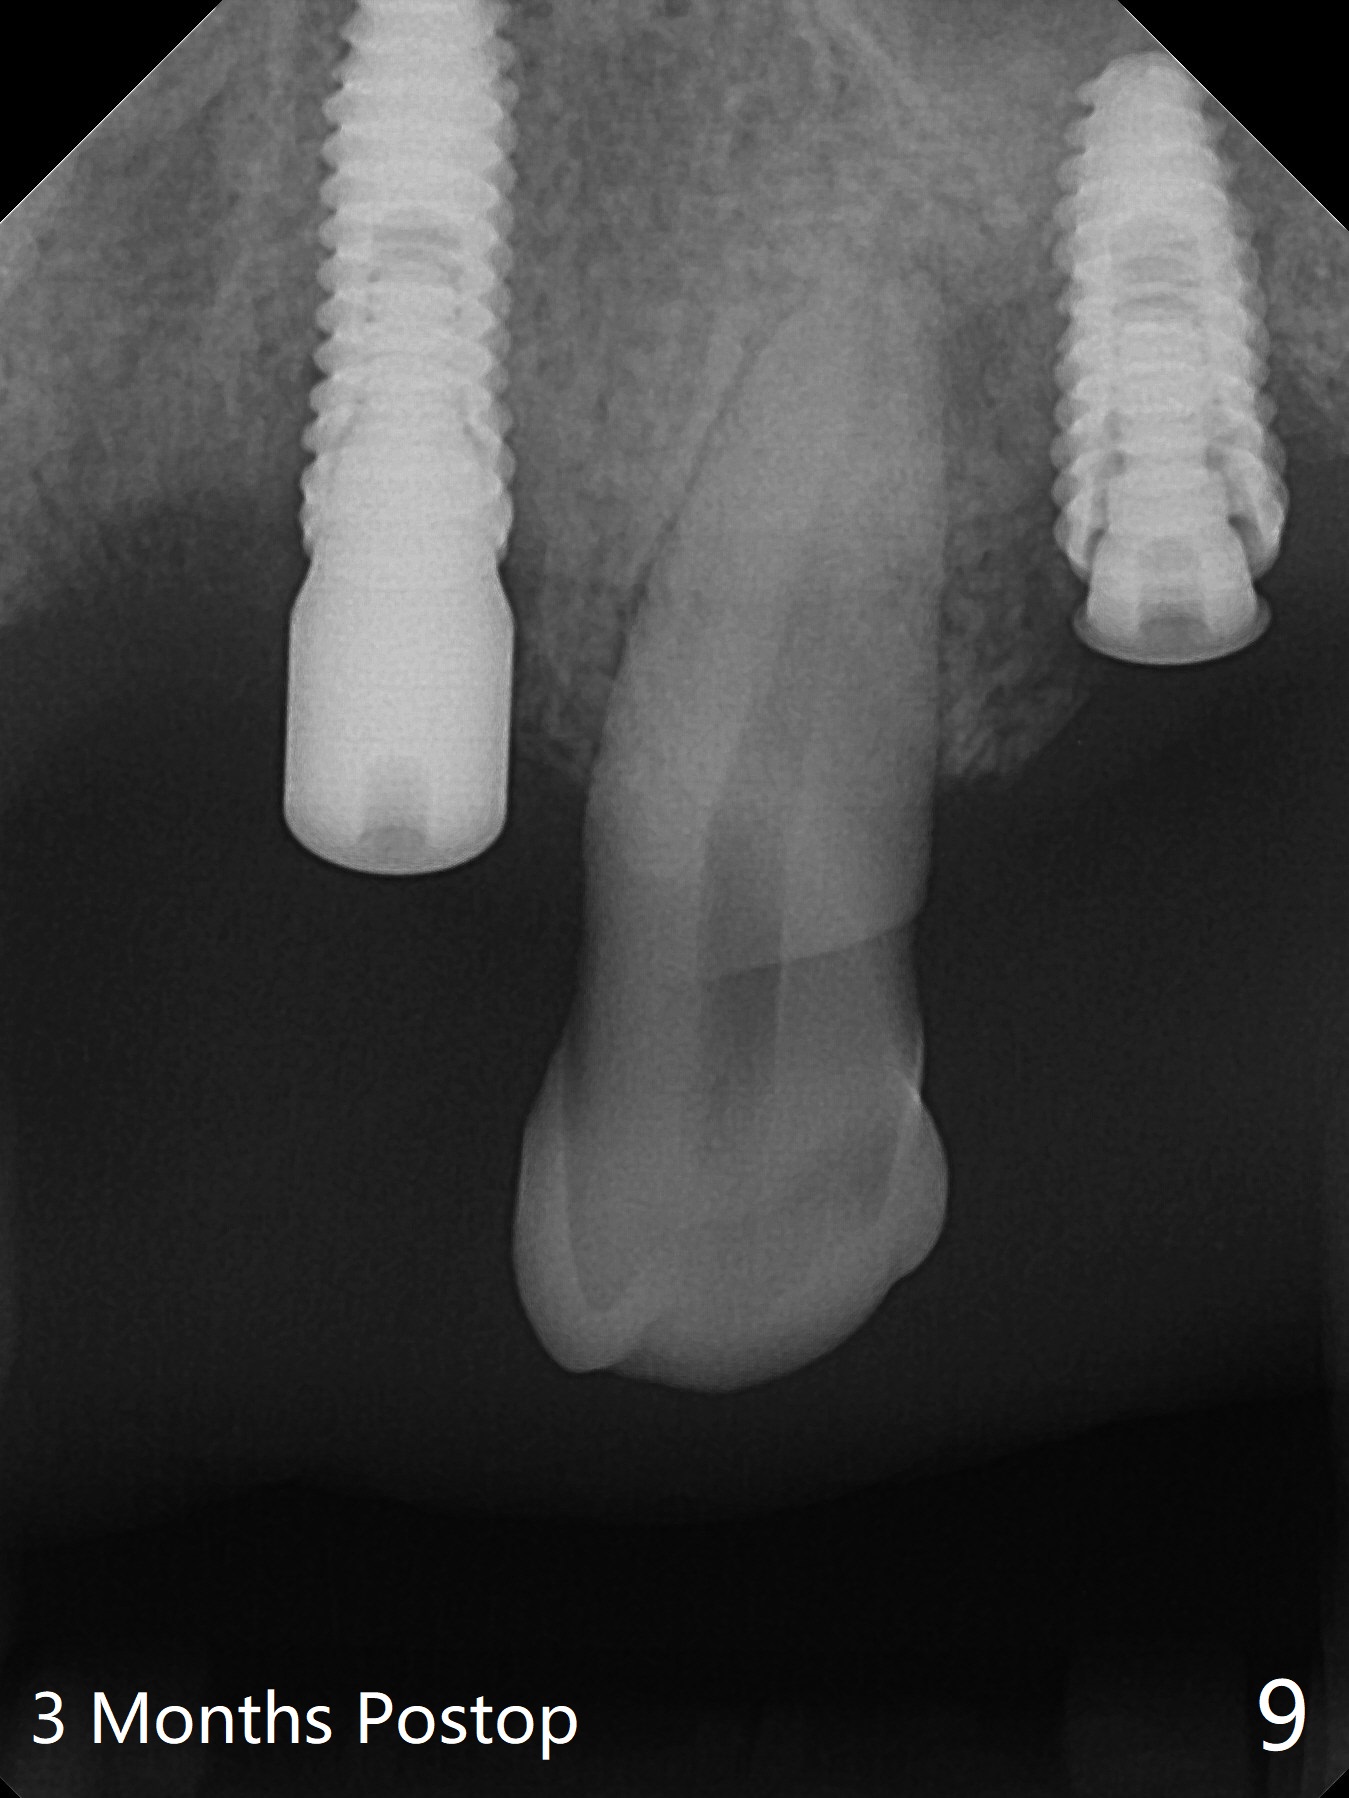

After a 4x10 mm implant is placed with fixture mounting (Fig.2 M) following sinus lift (*) at #12, osteotomy is initiated at #10 (Fig.1 (T: tube of surgical guide)). It appears that the drill (D) has good trajectory (between the Incisive Canal (red dashed line) and the canine root). The final position of the implant at #10 is acceptable (Fig.3). The implant at #12 is placed deeper (Fig.4 (arrow), as compared to Fig.2) because of clinically buccal superficial placement. The most critical challenge is anterior deep bite associated with posterior collapse. Periodontal dressing is applied. When the latter dislodges, there is minimal clearance for a provisional. Periodontal dressing is re-applied. The patient (smoker, partial edentulism with occlusal interference) returns for provisional nearly 1 month postop with chief complaint "something is lost in the back". In fact the healing abutment at #12 is lost with buccal granulation tissue (Fig.5). When a new abutment is seated, there is discomfort. When a healing screw is placed, it cannot be seated completely with two separate trials (Fig.6,7). Should we leave it as it is or open up for complete seating? It appears that the implant is loose. After preparation for clearance at #10, the abutment is retightened. It appears to turn with the underlying implant with discomfort. A 4x5 mm healing abutment is placed to reduce micro-movement. One week later, the infection at #12 dissolves with oral Amoxicillin (Fig.8). Due to limited occlusal clearance and implant tenderness when the abutment abutment is retightened, the cemented abutment is changed to a healing abutment. The implant at #10 seems to be osteointegrated, while the healing screw at #12 remains incomplete seating 3 months postop (Fig.9). The loose healing screw cannot be retightened securely, as there is bone loss around the implant 3 months postop (Fig.10 *). When a 4.5 mm x 15 degree 4 mm cuff angled abutment is placed, the mesiodistal trajectory improves (Fig.11), but there is no occlusal clearance (Fig.12). The latter would form when posterior support is established (Fig.13, either removable appliance (which the patient hates) or fixed one (finance)). Fig.14 shows the unhealed site of #12. Incision confirms the bone loss around the implant, which is removed. Although the sinus floor is absent, there is no membrane perforation. After debridement, allograft mixed with small amount of Osteogen is placed (Fig.15,16 G) and covered with Osteogen plug and 6-month membrane.